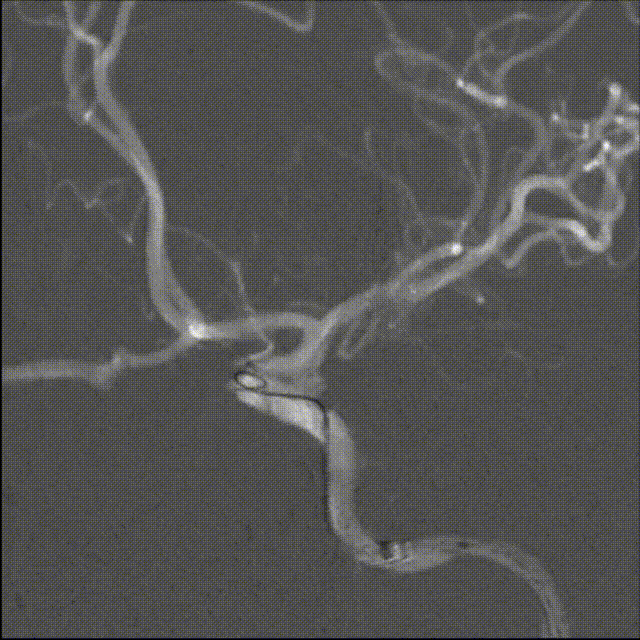

术后影像

➢术后工作位造影

病人术后:动脉瘤已完全栓塞,瘤体不显影,载瘤动脉通畅。